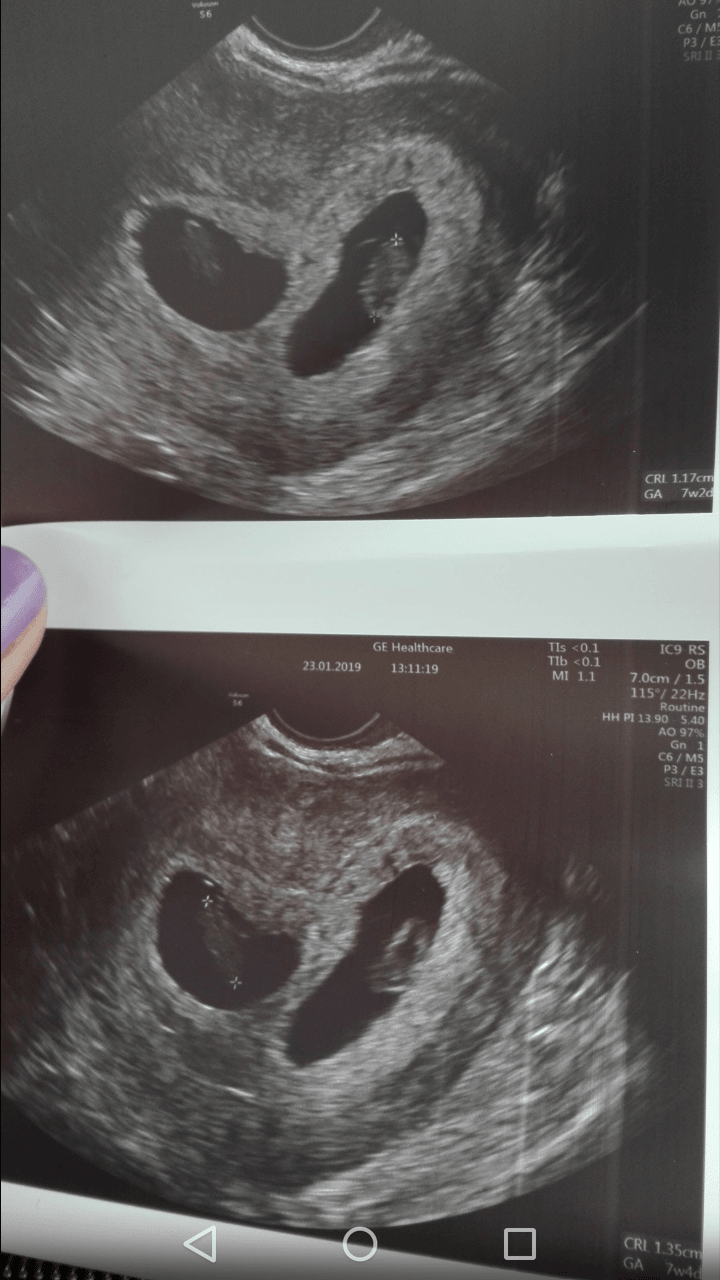

Dziewczyny pochwale sie i tu:D

Dzis 7+4.

Screenshot_2019-01-23-17-06-29.png

Screenshot_2019-01-23-17-06-13.png